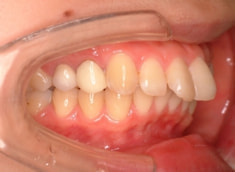

治療後(1年9ヶ月後)